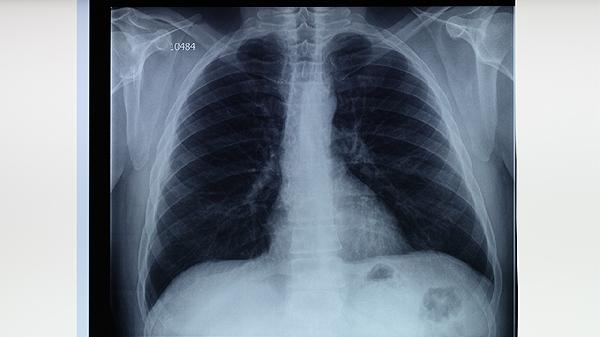

感冒后如出現(xiàn)上述癥狀持續(xù)不緩解,建議及時就醫(yī)進行結(jié)核菌素試驗、胸部X線或CT檢查。確診肺結(jié)核后需嚴格遵醫(yī)囑完成6-9個月的抗結(jié)核治療,避免擅自停藥導(dǎo)致耐藥。日常生活中應(yīng)注意保持室內(nèi)通風(fēng),均衡飲食,適當鍛煉增強免疫力,肺結(jié)核患者咳嗽時應(yīng)掩住口鼻,痰液需消毒處理。